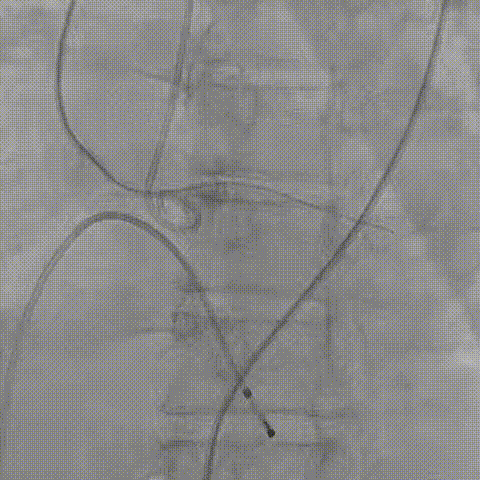

患者病史 主诉:发作性胸闷憋喘半年,加重伴呼吸困难2周。 现病史:患者半年前无明显诱因出现胸闷、憋喘,伴有下肢水肿,2周前上述症状明显加重,夜间不能平卧,痰中带血丝,为进一步诊治再次来我院,门诊以"心力衰竭"收入院。 既往史:肾功能不全、心房颤动 心脏超声提示:LVEF:0.54 1.主动脉瓣病变;2.主动脉瓣狭窄(重度)并反流(中度);3左室壁节段性运动不良;4.升主动脉扩张、双房扩大、左室肥厚;5.二尖瓣硬化并反流(中度);6.三尖瓣反流(轻-中度);7.肺动脉瓣反流;8.肺动脉高压(轻度)PGmean=105mmHg,Vmax=635cm/s,瓣口面积0.27cm²。 术前CT评估 Type0型二叶瓣,重度钙化,钙化集中在瓣叶游离缘,右冠窦为著;左冠高度11.8mm,由于左冠窦部空间较小,左冠风险较高, 升主动脉扩张,最宽处50.5mm;主动脉瓣环水平夹角61.5°,横位心。主动脉弓角77.6°,锐角弓,外周入路在腹主及髂总处有大量散状钙化,胸主处有81.6°的迂曲。 手术策略 推荐右侧股动脉为主入路,左侧股动脉为辅入路,送snare辅助过弯,使用18F大鞘,推荐预装ProStyle A® AV23瓣膜,20mm球囊预扩,初始定位对齐真实瓣环瓣上5mm超高位初始定位释放,释放过程中使瓣膜自然下滑,到工作位观察瓣膜形态,最终理想位置0-瓣下3mm。 手术过程 Step1:右侧股动脉为主入路、左侧股动脉为辅入路,成功穿刺并送入 18F 大鞘; Step2:主动脉根部造影,瓣口限制重 Step3:Type 0 型二叶瓣畸形合并重度钙化,患者瓣口狭窄严重,同时横位心,不仅导丝跨瓣困难,导管更难进入;术者凭借精湛操作,将导丝顺利跨瓣,反复微调导管角度,最终导管顺利过瓣。 导丝精准跨瓣 Step4:20mm球囊跨瓣困难,snare辅助下球囊成功跨瓣,预扩有腰无漏,冠脉充盈良好。 Step5: snare辅助下成功跨瓣,可以看到系统过弓形态瓣膜仓柔软,过弓顺滑 输送系统过弓 Step6:初始定位瓣上5mm开始释放,释放部分后观察瓣架下缘内收明显,后回收系统重新定位 初始定位 底部内收 Step7:瓣膜完全释放前,血压一度降低,术者迅速调整器械,实现瓣膜迅速锚定,快速释放 完全释放 Step8:20mm球囊后扩 最终造影,位置(瓣下3mm)形态良好 手术难点 患者不仅有主动脉瓣重度狭窄,还叠加肾功能不全、心房颤动等基础疾病,术中血流动力学波动极易引发心功能衰竭。ProStyle A® 预装干瓣“开包即用” 的特性压缩了术者操作时间,80%可回收设计给了术者容错空间,而这些看似难以逾越的难关,最终被团队精湛的医术一一化解,术中对于导丝、导管、球囊等器械每一步的精准操控,再到突发状况的从容处置,无不彰显着团队深厚的专业积淀与顶尖的操作技艺。 结语 此次手术的圆满成功,不仅彰显了陈玉国、李传保教授团队在复杂结构性心脏病介入治疗领域深厚的专业造诣与攻坚克难的决心,也充分验证了ProStyle A®系统在应对复杂高难度病例时的卓越适用性与有效性。 作为扎根齐鲁、享誉全国的医疗高地,山东大学齐鲁医院始终赓续着这片热土的仁厚文脉,将“医道从德,术业求精”的院训精神镌刻在每一次诊疗实践之中。特别是在结构性心脏病诊疗领域,医院团队始终怀揣医者担当,勇攀医学高峰,不断以更前沿的技术突破,为危重患者点亮重获新生的希望。 专家简介 陈玉国 山东大学齐鲁医院(点击查看专家详细简历) 李传保 山东大学齐鲁医院(点击查看专家详细简历) · END ·